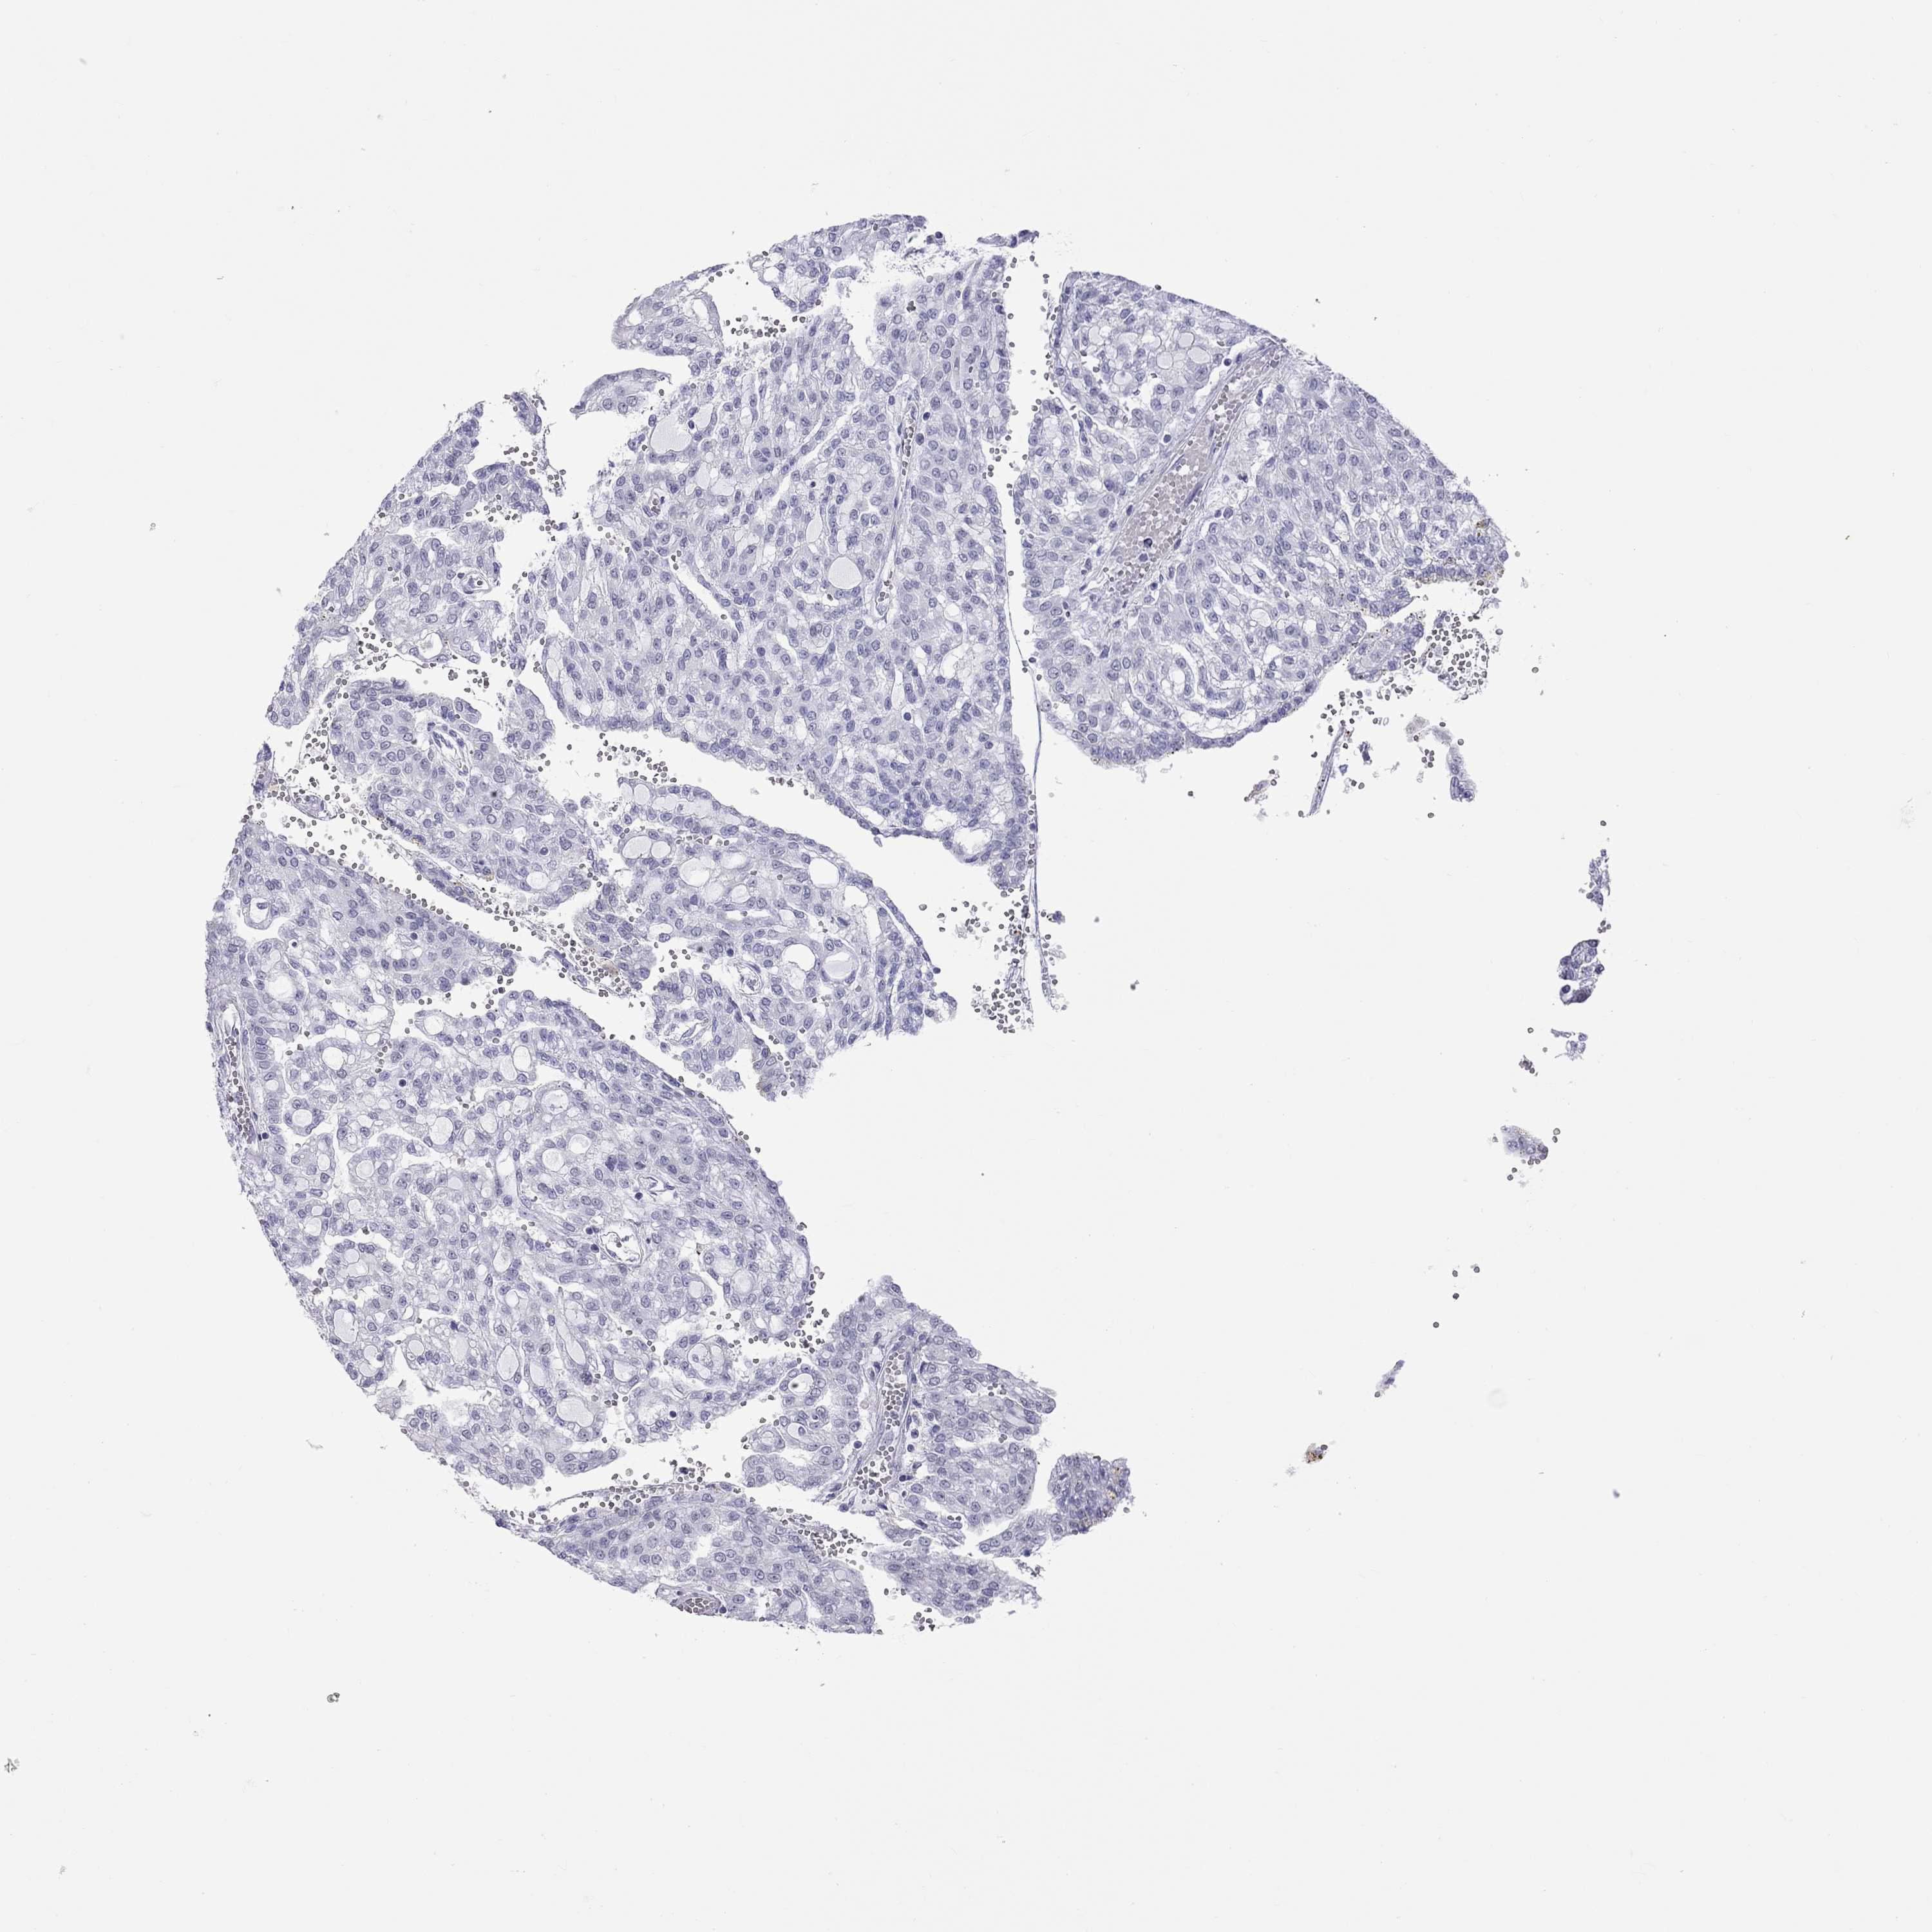

KICH TCGA KIRC TCGA KIRC VALIDATION KIRP TCGA PROTEIN RCC CPTAC PROTEIN EXPRESSION

Kidney renal papillary cell carcinoma